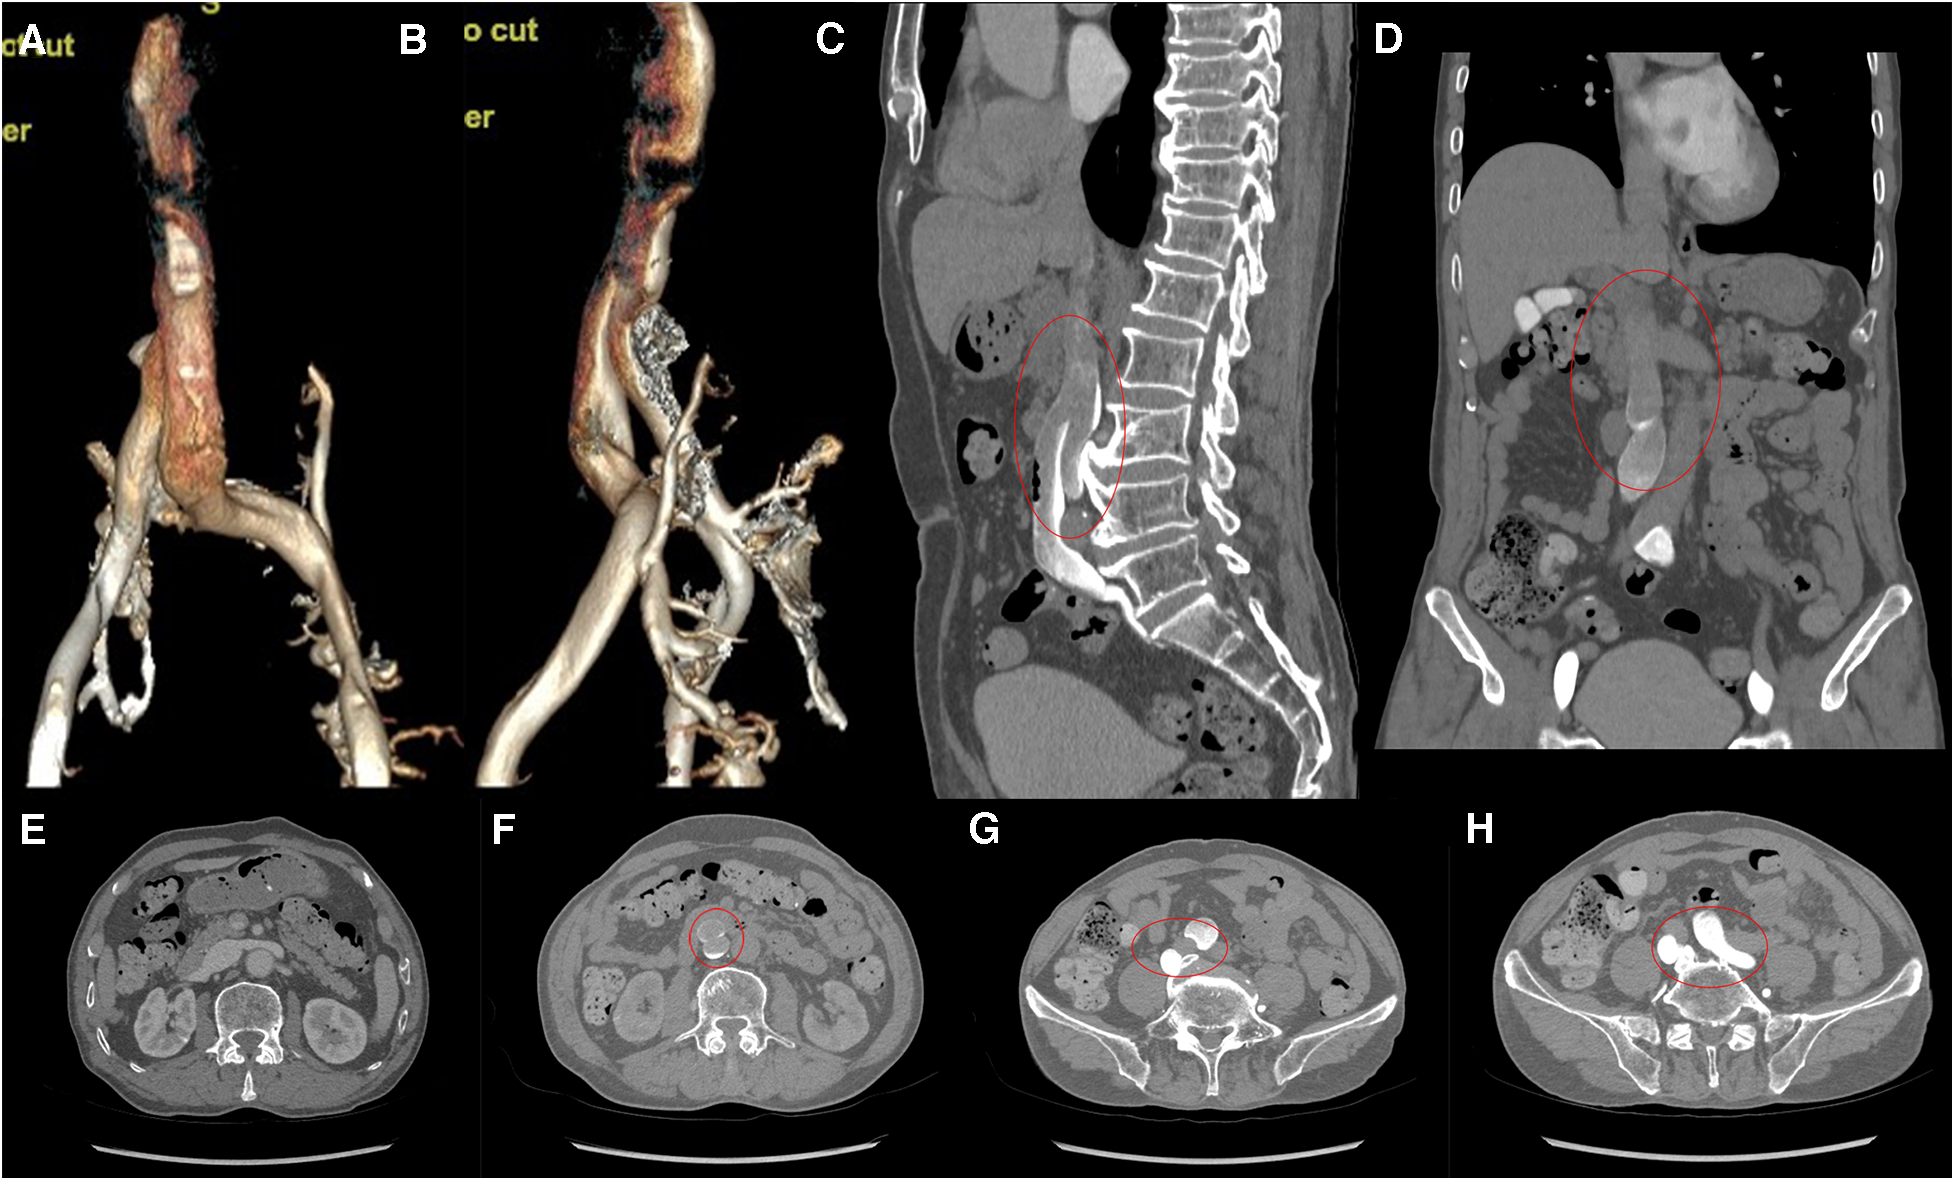

Computed tomography venography (CTV) revealed bilateral lower limb iliac vein lumen stenosis with paravalvular formation around and in front of the sacrum (Figure 2). Distorted and thickened vascular shadows were seen in the bilateral calf muscle spaces, especially on the left side. Then, CTV of IVC suggested that the left common iliac vein traveled cranially and crossed the bifurcation of the common iliac artery, and continued cephalad as a ventral vessel, while the right common iliac vein extended cephalad as a dorsal vessel. The dorsal vessel was narrowed at the level of 4th lumbar vertebrae, by the compression of the hyperplastic bone and the osteophyte (Figure 3). Both vessels run parallel to the abdominal aorta and converged on the right side of the abdominal aorta, at a level where bilateral renal veins converge 12.5 mm pedal to the IVC. The suprarenal segment, renal segment and bilateral renal veins of the IVC are normal.

Figure 3

(A,B) VR images of CTV of IVC. (C,D) MPR images of the sagittal and coronal venous phases of IVC, showing DIVC in a ventral-dorsal relationship (red oval), confluent at the level of 3rd lumbar vertebra. (E) Plain scan, with normal development of the bilateral renal veins where they converge into IVC. (F–H) Images of the axial venous phase, with the inferior renal segment of the IVC divided into two ventral and dorsal branches. The left common iliac vein crosses between the bilateral common iliac arteries to join the ventral vessel, and the right common iliac vein joins the dorsal vessel.